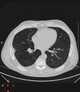

Bronchial lesion

Bronchiectasis

Multiple pulmonary nodules

Obstructive pneumonia

Recurrent pneumonia

Solitary pulmonary nodule

Unilateral pulmonary edema